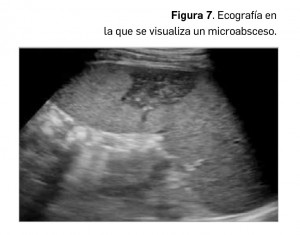

El contexto clínico suele incluir: fiebre, mal estado general y dolor en el hipocondrio izquierdo, no siendo el hallazgo casual de esta afección en absoluto frecuente. Los pacientes inmunodeprimidos son proclives al desarrollo de afectación esplénica infecciosa, habitualmente por diseminaciones fúngicas, siendo la más frecuente la candidiasis generalizada, seguida en frecuencia por la aspergilosis y la criptococosis. Los pacientes con tuberculosis miliar diseminada también suelen presentar afectación esplénica múltiple, habitualmente en forma de microabscesos. Los microabscesos esplénicos se manifiestan como lesiones milimétricas de baja ecogenicidad (Figura 7), dispersas en el parénquima esplénico, acompañándose de esplenomegalia.